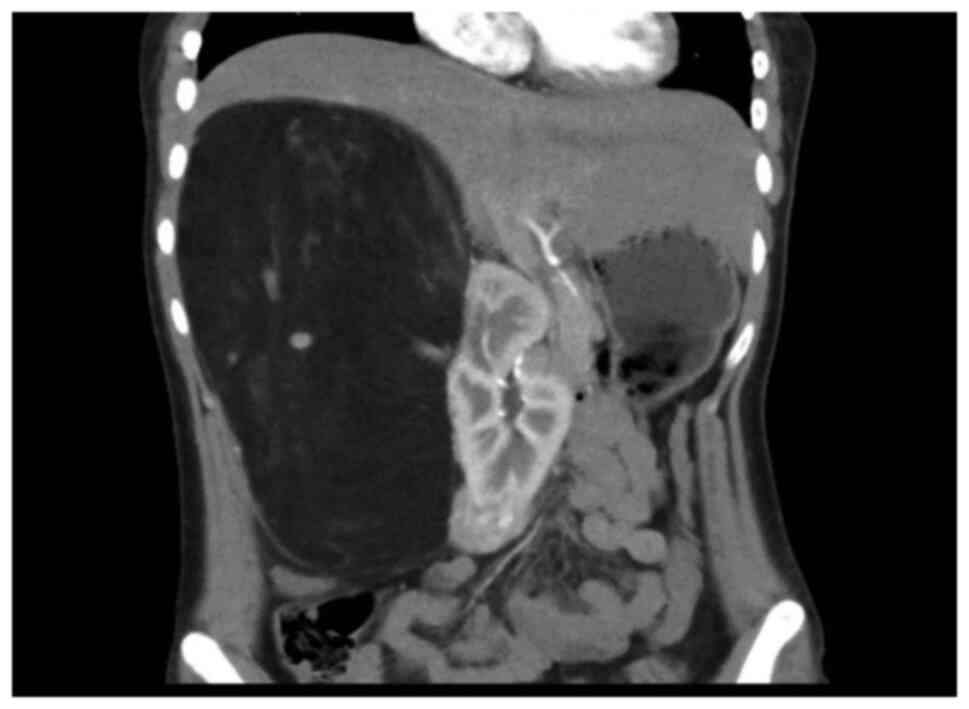

The 20-year-old young female patient has been diagnosed with epilepsy since childhood and has been treated with valproate sustained release tablets. She was admitted to the department of neurology of our hospital due to repeated daze, occasionally accompanied by nausea, vomiting, and hallucinations. Physical examination showed that the patient was slightly slow in response and expression, and her calculation was poor. Multiple small papules and nodules can be seen on her cheeks. Palpation of the right upper abdomen revealed a tough mass with smooth surface, fixed position, and no tenderness. Valproic acid test in the laboratory showed that the patient's CYP2C9 genotype was CYP2C811, and the enzyme activity was fast metabolism (EM) type. POLG (A467TG>A) was of wild homozygous type, POLG (W748SC>G) wild homozygous type SLCO1B1 genotype was 1b1b, and ApoE genotype was E2E4. The electrolyte, liver enzymes, renal functions, cardiac functions, routine examination of blood and urine, and coagulation functions were normal. Abdominal enhanced CT scan showed that the liver was obviously pushed, and the spine was scoliotic. A huge mass occupied the right upper quadrant, with a size of ~236x125x149 mm. The CT value was about-78HU. Blood vessels could be seen inside, and the boundary between the blood vessel and the kidney was unclear. The surrounding tissue was pushed, and the right kidney was displaced to the middle abdomen (Fig. 1). Moreover, two inhomogeneous enhancement nodules were present in the middle and lower pole of the right kidney. The larger nodule (26x33 mm in size) was in the right kidney. Multiple low-density shadows with no enhancement were also evident in the right kidney. In the left kidney, an inhomogeneous enhancement nodule was present on the upper pole, and its size was 28x29 mm. Multiple no enhancement low-density shadows (Fig. 2) were distributed in the left kidney. The right adrenal gland was unclear. The shape, size, and density of the left adrenal gland were normal. No obvious dilation and hydrops were observed in the bilateral renal pelvis and calyces, and the intestinal curve was pushed. No obvious enlarged lymph nodes and no ascites signs were seen behind the peritoneum. The result of the Chest CT scan showed multiple nodular shadows with sizes of ~2-3 mm in the right upper lobe and dorsal right lower lobe. A nodular shadow, ~3 mm in size, was seen under the pleura of the tongue of the left upper lobe. Cranial MRI showed the following results. Abnormal signals were detected from the bilateral cerebral hemisphere cortex, right putamen, and right caudate nucleus. A slightly low signal was observed in T1WI. A slightly high signal was observed in T2WI and FRAIR. The DWI showed no diffusion with limited high signal. Under the bilateral maxillary sinus mucosa, round-like long T1 long T2 signal shadows were seen, and the larger one was ~15x17 mm in size. Considering the patient's medical history and the results of laboratory examination, the diagnosis included epilepsy, giant hamartoma of the right kidney, hamartoma of the left kidney, multiple pulmonary nodules, and abnormal head signals, which were highly consistent with the manifestations of TSC. Although the patient had no obvious symptoms of abdominal visceral compression, and laboratory examination showed no obvious abnormalities in the kidney function. The compression of a huge abdominal mass caused the liver and kidney to deviate significantly and led to spine scoliosis. The continued growth of the mass may affect the function of the kidney and the digestive system. Moreover, the overgrown mass puts the patient at risk of spontaneous rupture and bleeding, which are life-threatening. So, the mass was indicated for surgical resection. After comprehensive preparation before the operation, the patient underwent open mass resection and right kidney partial resection. The appearance of the tumor is shown below (Fig. 3). Postoperative pathological results (Fig. 4) confirmed RAML, and the immunohistochemical results were as follows: HMB45 +, SMA +, Des +, S100 +, and Ki67 (1% +) (Fig. 5). The patient recovered smoothly after the operation. No recurrence of kidney tumors was found. Nodules in the lungs and abnormal head signals remained the same after the half-year follow-up period.

Figure 1

A huge mass in the right kidney. The surrounding tissue is squeezed.